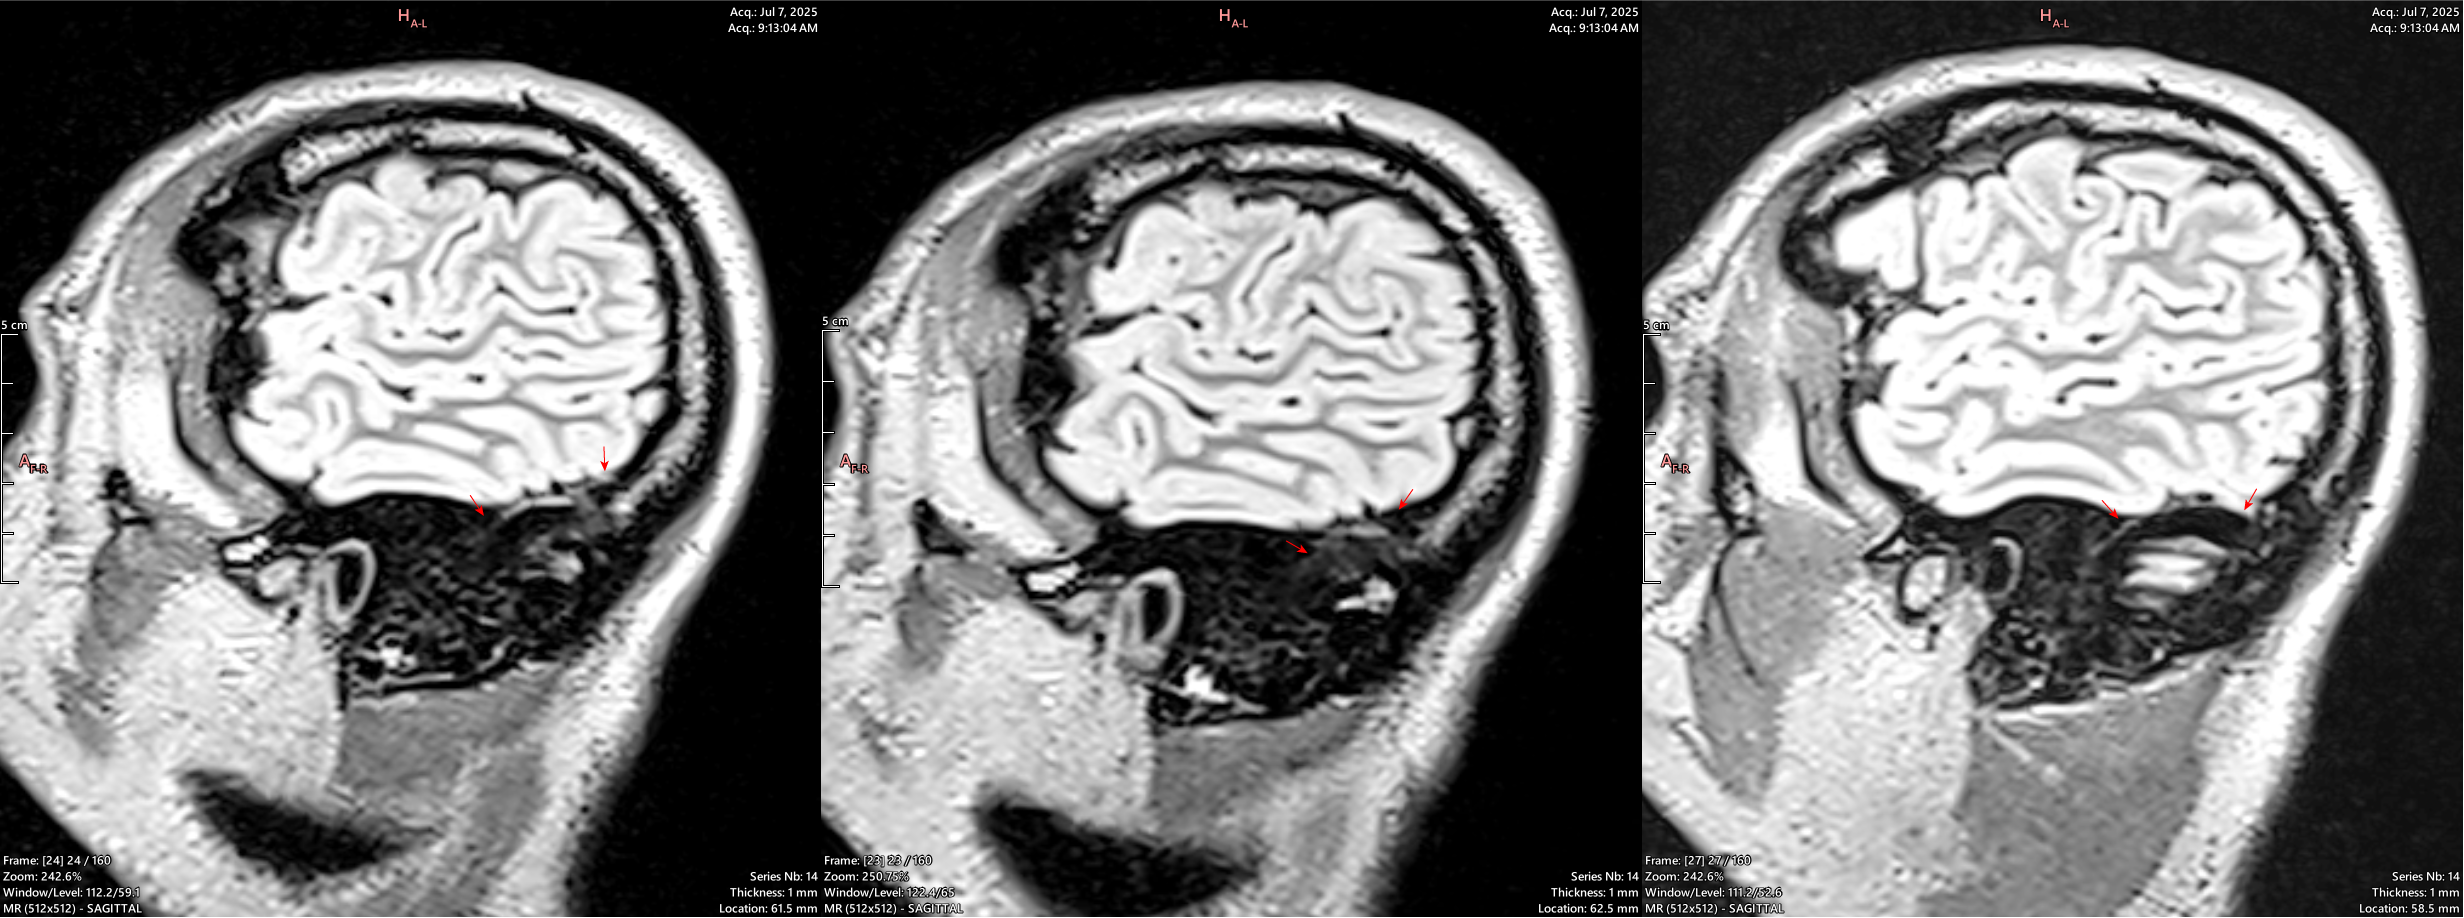

The same slice shown above (right), with a wider window setting to better demonstrate what is actively happening in this area.

There is hypointense soft tissue signal throughout the areas of skull destruction, including in the cortical layer of the skull (black signal out table of the bone). This demonstrates an active pathological process of osteolysis occurring, in which the bone is destroyed and replaced by this tissue.

These are corresponding slices from 2 MRI series performed in OCT 2024 (left) and JULY 2025 (right). They show progressive, pathological boney change and osteolysis (bone destruction) over the 9 months between imaging. The yellow (OCT) and green (JULY) lines highlight visible and active bone destruction.

The pink is a significant region of interest as it shows not only the destruction of bone, but a “caving-in” change in the bone shape; Interestingly, this change is physically visible on the scalp as depicted below.